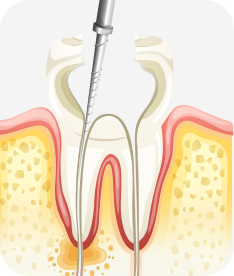

신경치료

자연치아를 살라기 위한 가장 기본적이고 중요한 치료입니다

치아 외상이나 충격, 깊은 충치 등의 이유로 치아 내부의 신경과 세포 조직에 염증이 생겼을 경우, 이 를 제거하고 소독하여 생체친화적인 특수 재료로 신경관을 충전해 치아의 기능을 유지할 수 있는 중요한 치료입니다.

3차원적인 신경관 내부를 치아 밖에서 도달하여 뿌리 끝까지 정밀하고 정확하게 치료해야 하는 신경치료는 가장 기본적인 자연치아 살리기 치료이자 고난이도 치료입니다.

치아신경 염증

충치가 심해져 치아 뿌리까지 신경 염증이 발생함

신경소독

충치를 제거하고, 치아 뿌리 끝까지 신경관 내부의 염증 물질들을 제거하고 소독함

신경치료 완료

소독된 신경관을 생체친화적인 재료로 충전한 후 보철치료를 함